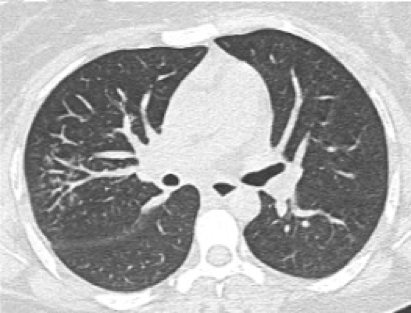

Opacidad en vidrio deslustrado y distribución periférica (subpleural)

La opacidad en “vidrio deslustrado” se define como un aumento ligero de la atenuación pulmonar que mantiene visibles los contornos bronquiales y vasculares.

Opacidad en vidrio deslustrado

Distribución subpleural o periférica (a menudo preservación central)

De predominio periférico, basal y generalmente bilateral

No nódulos, no derrame, no cavitaciones